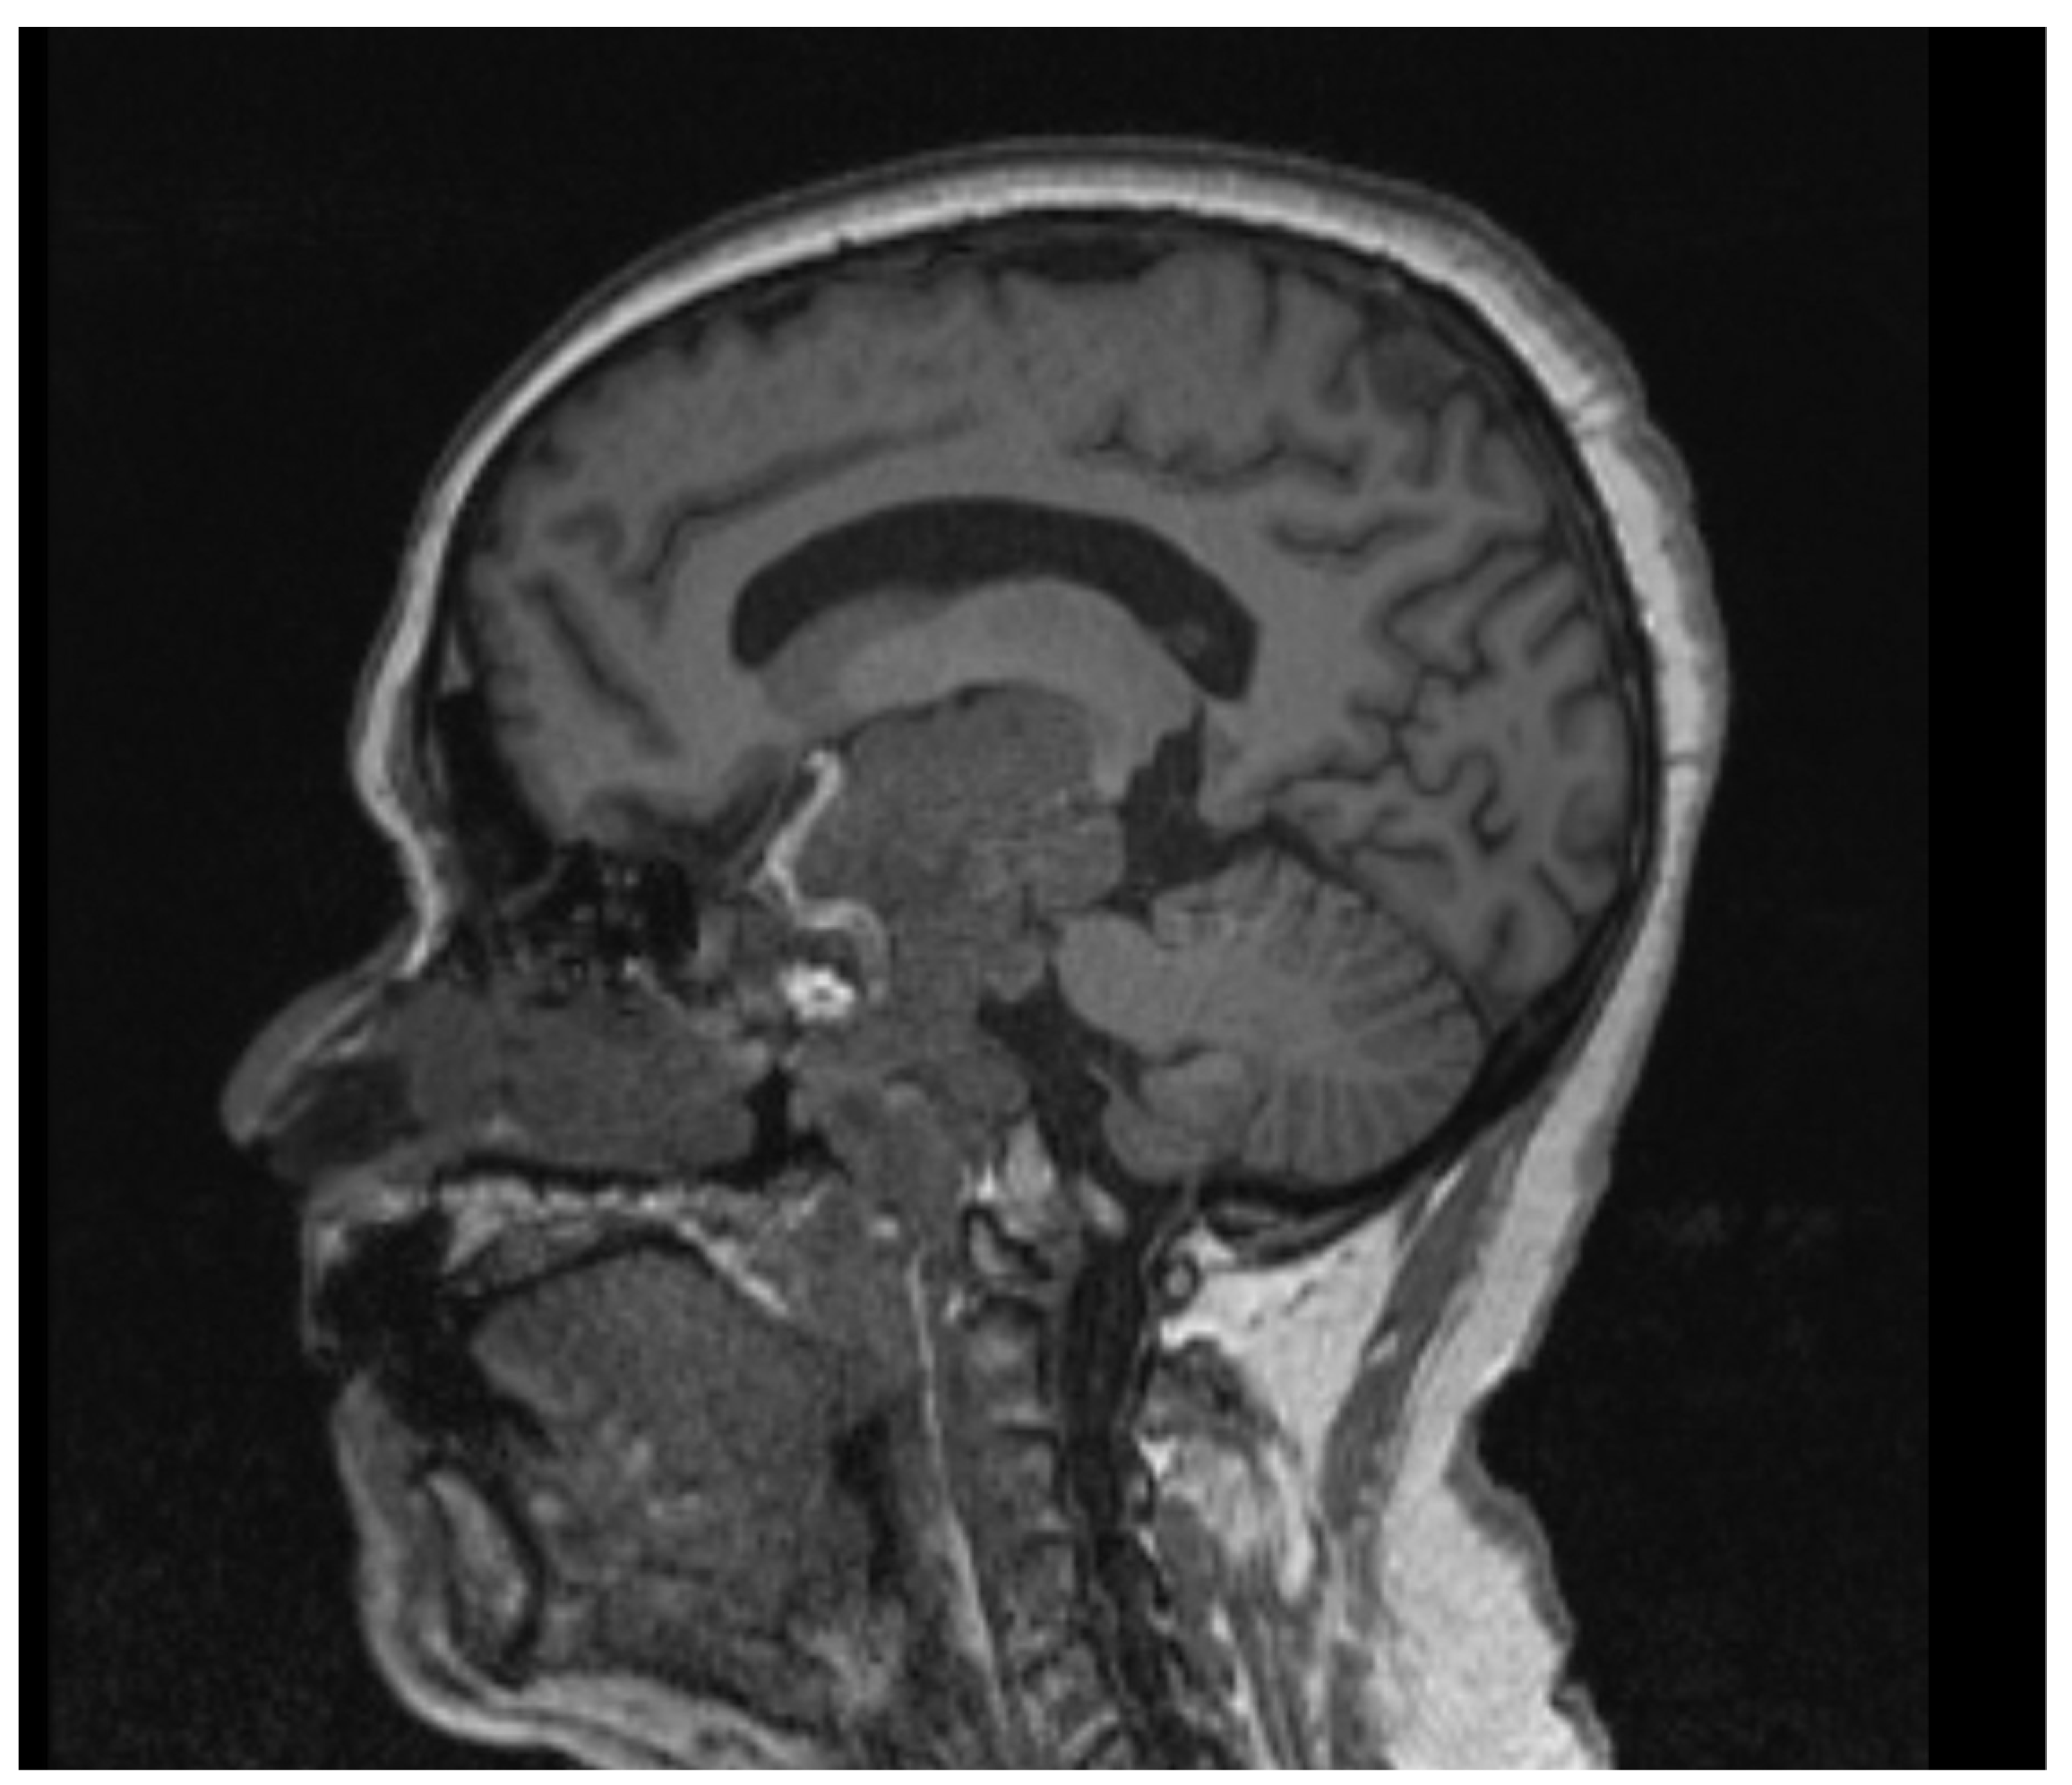

2.1. Case 1

2.2. Case 2